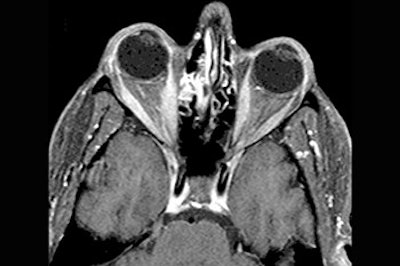

Axial (top) and coronal (below) contrast-enhanced, fat-suppressed T1-weighted images through the orbits demonstrate diffuse homogeneous thickening of the medial, lateral, and inferior rectus muscles of the right orbit. There is minimal thickening of the superior muscle group. The tendinous insertions are not involved. There are also scattered inflammatory changes in the ethmoid sinuses and the left maxillary sinus.![]() |

The patient underwent MR imaging on a 1.5-tesla Signa scanner (GE Medical Systems, Waukesha, WI). Gadolinium-enhanced, fat-suppressed, T1-weighted images were obtained through the orbits. Contiguous images of 4 mm with a 1-mm interslice gap in the axial and coronal planes were obtained, Som told AuntMinnie.com.

Prior to treatment, the MR scans showed "diffuse homogenous thickening of the medial, lateral, and inferior rectus muscles of the right orbit." In addition, scattered inflammatory changes in the ethmoid sinuses and left maxillary sinus were seen, the group reported.